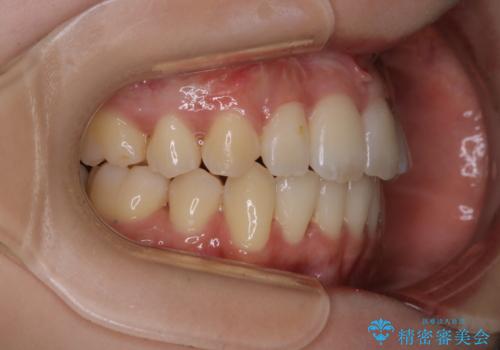

がたつきが強いガチャ歯。埋伏歯抜歯+矯正。すごいところに犬歯が埋まっていたのを抜いてワイヤー矯正治療

- 歯のがたつきを主訴に来院されました。

がたつきの強さから4本抜歯の必要性がありましたが、右上の歯は犬歯が一本埋まっており、乳歯がある状態でした。

結果的に見た目の違和感もなく、期間の短縮にもつながりました。